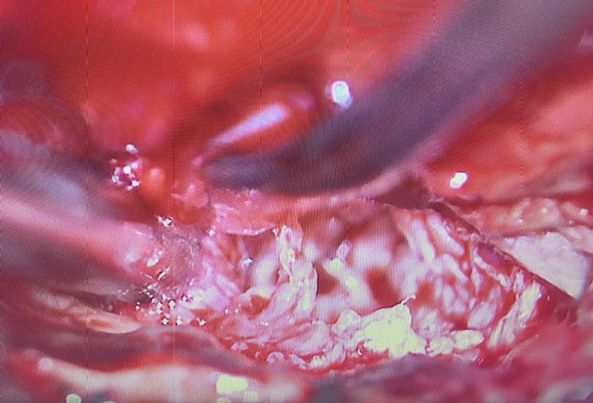

Microscope assisted single level discectomy and fluoroscope-assisted root block. All thanks to Dr. Ariful Islam. This type of surgery Is recommended for young individuals with single-level posterior disc protrusion and related issues (preferably one-sided). The upside is faster recovery, preservation of original bone structures, and no need for instrumentation (eg. screws, etc.).